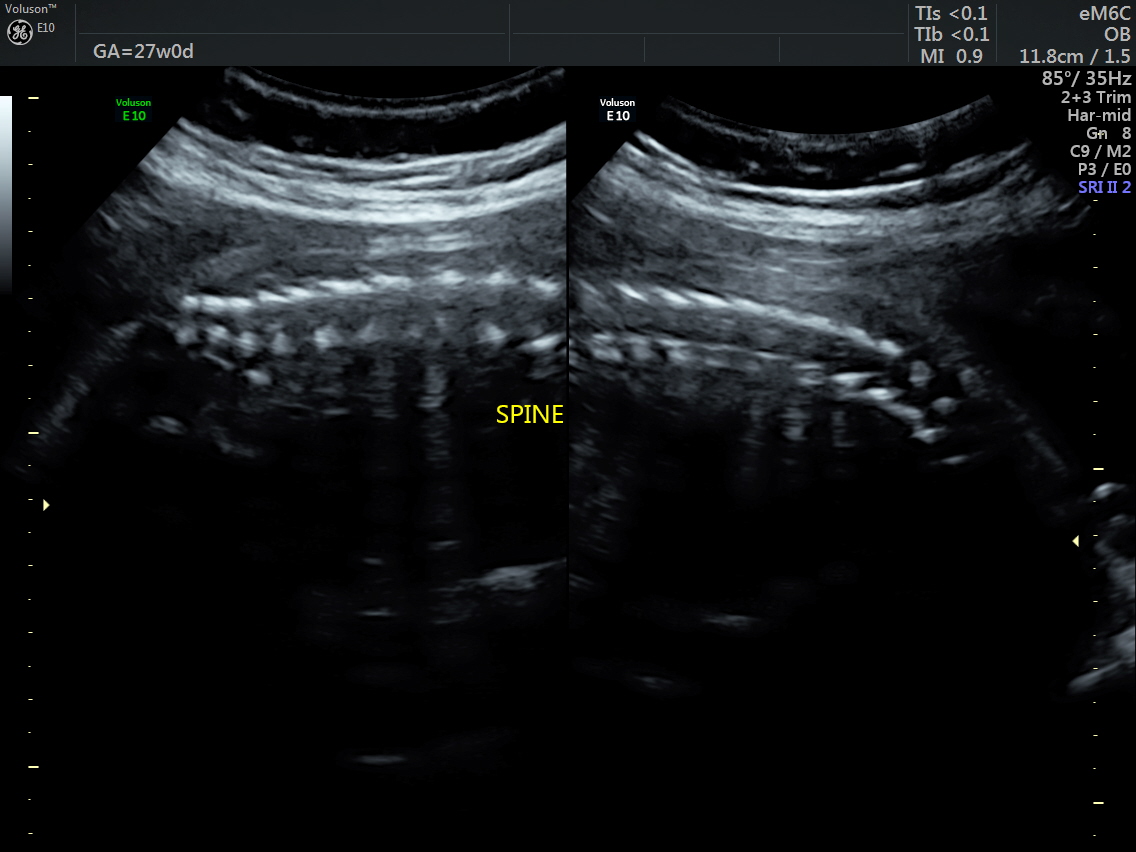

RT AORTIC ARCH_34 Published June 17, 2016 at 1136 × 852 in Rt aortic arch and aberrant left subclavian artery ← Previous Next →